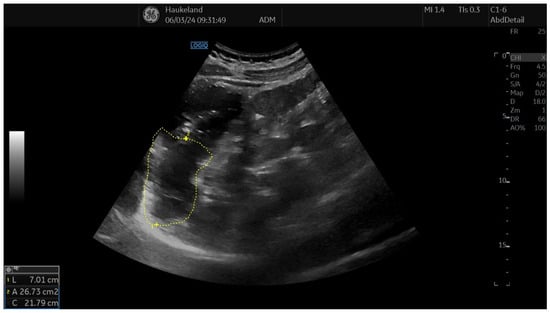

The most common method applied to assess proximal gastric accommodation was by assessing changes in proximal gastric area (PGA) and maximal proximal gastric diameter (MPGD). Changes in PGA and MPGD after meal ingestion were used as indirect measurements of proximal gastric volume changes, thus reflecting gastric accommodation. To obtain PGA, the transducer was placed in the epigastrium longitudinally under the left subcostal margin and tilted cranially in the long axial direction [11,12,18,22]. This allowed for a visualization of a sagittal section of the proximal stomach, and internal landmarks were the left kidney in the longitudinal projection, the left lobe of the liver, and the tail of the pancreas [11,12,18,22]. On the sagittal section, PGA was calculated by tracing along the luminal echogenic surface, which corresponded to the interface between the gastric liquid and the mucosa of the gastric wall (Figure 3) [11,12]. This was performed from the top margin of the fundus to 7 cm inferiorly along the axis of the proximal stomach (Figure 3) [11,12,18,22]. MPGD was obtained from an oblique frontal section (transverse section), which was achieved by rotating the probe 90° clockwise and tilting it cranially in the short axial direction [11,12,18,22]. The landmarks to look for in the transverse section were the left hemidiaphragm, the top margin of the fundus, and the liver parenchyma [11,12,18,22]. The diameter was measured within the 7 cm long axis of the proximal stomach (Figure 4) [18,22].

Figure 3. This image shows a measurement of proximal gastric area (PGA) using 2D-US in sagittal section, and this is used to assess gastric accommodation. PGA was obtained by placing the transducer longitudinally under the left subcostal margin and tilting it cranially in the long axial direction. Internal landmarks to look for were the left kidney in the longitudinal projection, the left lobe of the liver, and the tail of the pancreas. PGA was calculated by tracing along the luminal echogenic surface, which corresponded to the interface between the gastric liquid and the mucosa of the gastric wall. This was performed from the top margin of the fundus to 7 cm inferiorly along the axis of the proximal stomach. This image was taken after meat soup ingestion as part of the ultrasound meal accommodation test (UMAT) that is regularly performed at Haukeland University Hospital, Bergen, Norway.